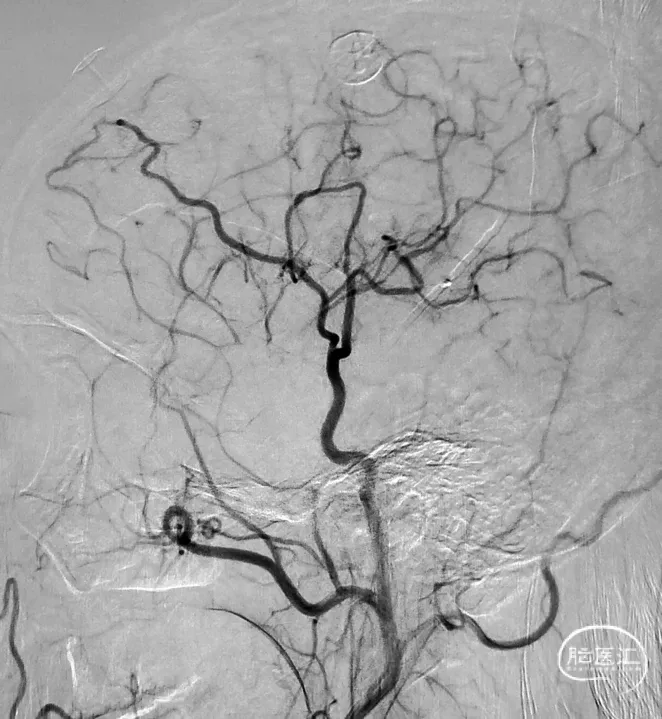

图7 STA-MCA吻合治疗MMD的术式种类